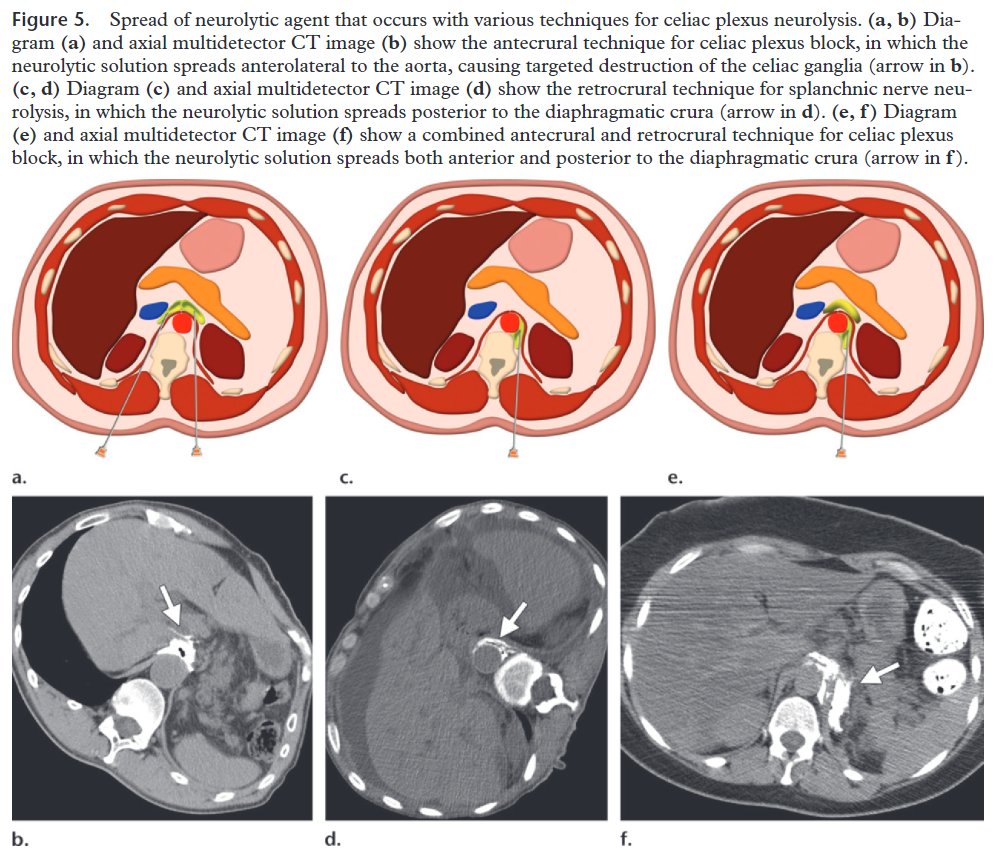

Alcoolisation rétrocrurale du plexus coeliaque

Alcoolisation rétrocrurale du plexus coeliaque à visée antalgique

Technique :

Geste réalisé sous anesthésie locale, sous contrôle scanner.

Repérage scanner retrouvant [XXX] et identifiant les espaces graisseux rétrocruraux entre T12 et L2, cibles du geste.

Sous contrôle scanner, mise en place dans l'espace graisseux rétrocrural cible de chaque côté d'une aiguille spinale noire 22G.

Injection de produit de contraste (1 ml de chaque côté). Confirmation par scanner de la bonne position des aiguilles.

Scanner de contrôle montrant une bonne diffusion craniocaudale du produit de contraste dans l'espace rétrocrural de chaque côté.

Alcoolisation bilatérale rétrocrurale du plexus coeliaque.